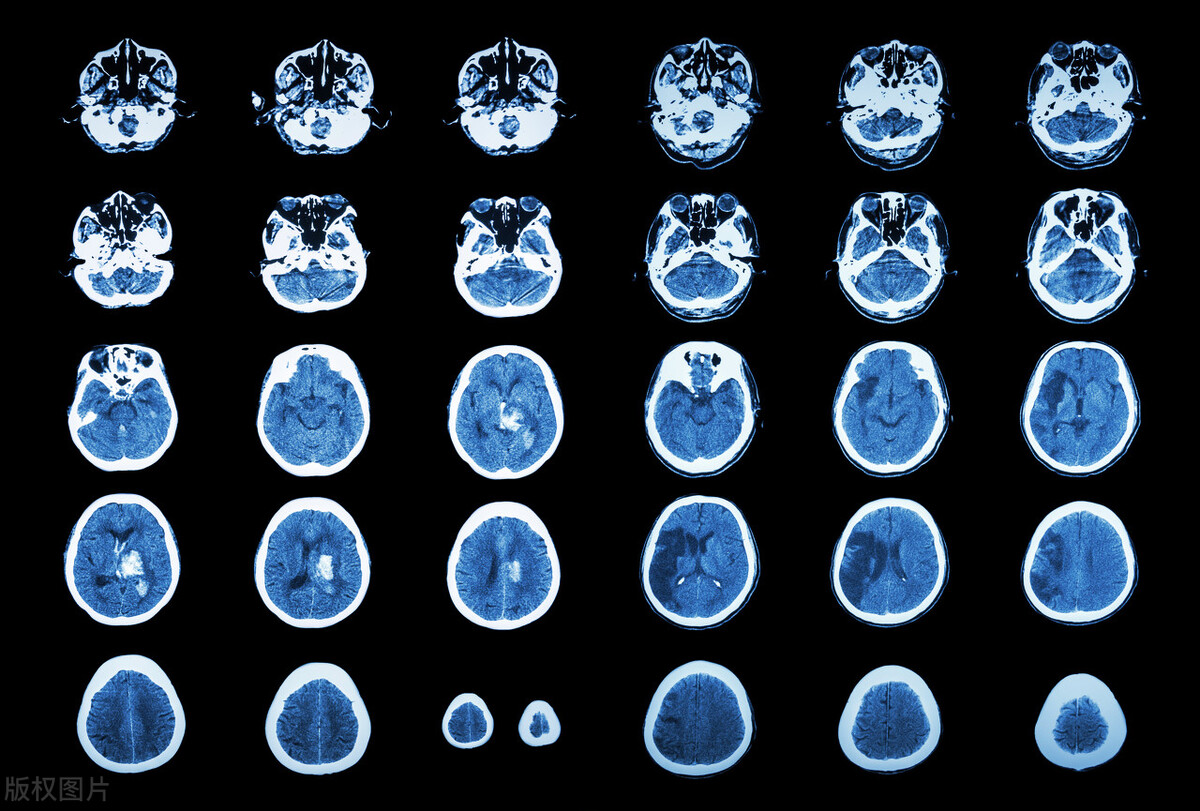

医生跟他说这个年纪的高血压老,是很容易突发脑出血性梗死的,死亡率很高,因此要时刻注意“脑出血”的问题。

因此,如果某一天,一股高强度的血流正好冲击了你最薄弱的脑血管,然后你的血管已经变得很脆弱,那就有可能被直接冲破,然后导致脑动脉出血。喷涌而出的血液会压迫患者的脑组织、脑神经,从而造成巨大的危害。

脑出血梗死是急性病的那一种,如果不及时清除病灶、止血,很有可能发生脑疝、脑死亡,因此在家中紧急处理的技巧,大家一定要懂。